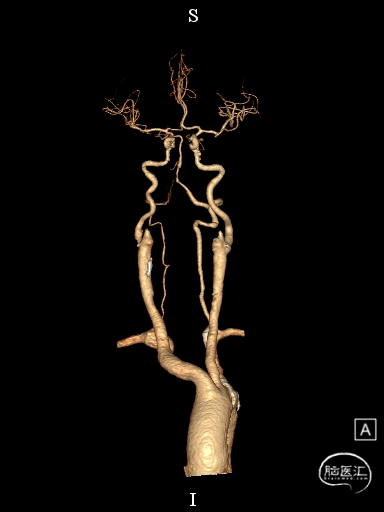

CTA提示:右侧椎动脉纤细,左侧椎动脉V1、V4段纤细。

右侧颈内动脉起始部中度狭窄,未见血流向后循环代偿。

左侧颈内动脉造影提示后交通开放,代偿供应后循环。

左侧椎动脉开口重度狭窄,前向血流缓慢,V4闭塞。

左侧椎动脉V4段闭塞、左侧椎动脉起始部重度狭窄、左侧小脑急性脑梗塞、右侧颈内动脉起始部狭窄。